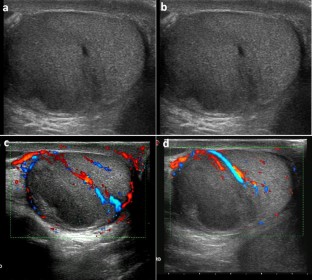

Intratesticular hematoma is one of the most frequent presentations of scrotal trauma. Ultrasound is the first-line imaging modality in the evaluation of scrotal trauma, and its findings are crucial for the choice of treatment. An intratesticular hematoma may represent a diagnostic pitfall for the investigating physician since its appearance may mimic other conditions, such as testicular neoplasms or segmental infarction. Although the gold standard imaging modality for the characterization of a testicular lesion is contrast-enhanced magnetic resonance (MR), MR equipment is not always available in an emergency department. Contrast-enhanced ultrasound (CEUS) may represent a valid and cheaper alternative compared with MR, which may aid the physician in the differential diagnosis. We describe the case of a 19-year-old male with a scrotal trauma following a motorcycle crash. In accordance with the literature, we carried out a contrast-medium whole-body computed tomography for the evaluation of any potential traumatic injury. Because of scrotal swelling and the patient complaining about pain in the right testicle, we performed a scrotal ultrasound, which demonstrated an enlarged right testicle, with an inhomogeneous echostructure due to the presence of a hypoechoic area in the middle and upper portion of the testicle. Color Doppler ultrasound did not show signals of intralesional vascularization. The lesion, although having characteristics compatible with hematoma, must not be diagnosed as testicular neoplasia, segmental infarction, or other mimics. For more information, a CEUS examination was performed. The examination clearly showed the extent of the lesion, the integrity of the testicular capsule, and the absence of internal vascularization; all these findings were regarded as indicators of a testicular hematoma. After the urological examination, the patient was prescribed antibiotic therapy and bed rest. For further confirmation of the CEUS examination, an MR was performed 2 days later, showing a perfect correspondence with the CEUS findings. Our case demonstrates that CEUS is a faster, cheaper, and valid alternative to MR in an emergency setting, as in testicular trauma, in which the hematoma may mimic conditions (neoplasm) that require a different treatment.

Fig. 3